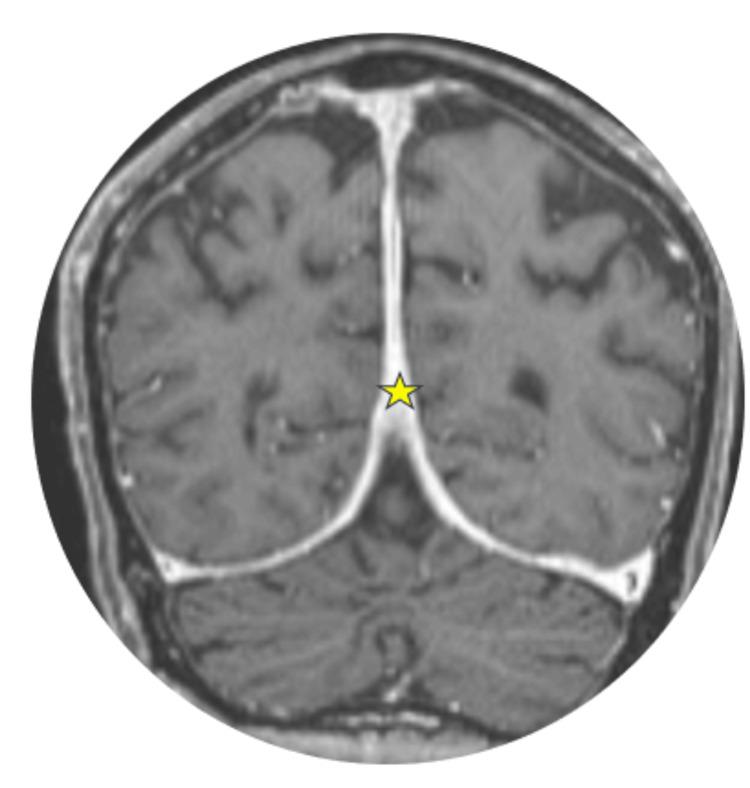

Erdheim-Chester disease (ECD) is a rare, multisystemic, non-Langerhans cell histiocytic neoplasm predominantly affecting middle-aged males in their fifth to seventh decades of life. It often presents with nonspecific symptoms, leading to a delay in its diagnosis. We report a case of an 85-year-old male with multisystemic manifestations, including retroperitoneal, skeletal, vascular, cardiac, orbital, and central nervous system (CNS) involvement. Imaging revealed characteristic findings such as bilateral osteosclerosis, perirenal infiltration (hairy kidney sign), and dural-based intracranial masses. Histopathological analysis confirmed the diagnosis, identifying CD68+ histiocytes and the BRAFV600E mutation. The patient was managed initially by Internal Medicine and later referred to Hemato-Oncology for further treatment. This report highlights the importance of maintaining a high index of suspicion for this rare disorder, as well as adopting a multidisciplinary approach toward its treatment, integrating clinical, radiological, and histopathological data.

Erdheim-Chester病(ECD)是一种罕见的、多系统的、非朗格汉斯细胞组织细胞肿瘤,主要影响50至70岁的中年男性。它常表现为非特异性症状,导致诊断延迟。我们报告一例85岁男性,有包括腹膜后、骨骼、血管、心脏、眼眶和中枢神经系统(CNS)受累的多系统表现。影像学检查发现了特征性表现,如双侧骨硬化、肾周浸润(毛肾征)和硬脑膜下颅内肿块。组织病理学分析确诊,发现CD68+组织细胞和BRAFV600E突变。患者最初由内科处理,后来转诊至血液肿瘤科进行进一步治疗。本报告强调了对这种罕见疾病保持高度怀疑指数的重要性,以及采用多学科方法进行治疗,整合临床、放射学和组织病理学数据。